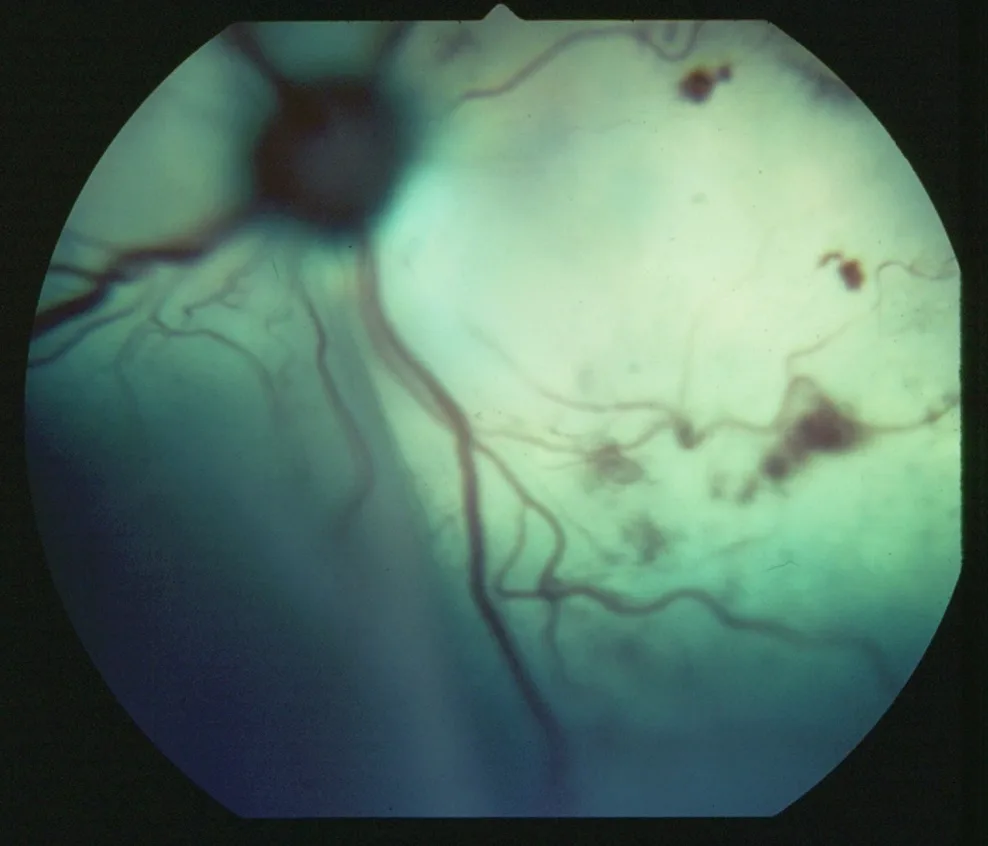

Intraocular image showing bright yellow-green tapetum containing several irregular patches of red.

FIGURE 4

Multifocal retinal hemorrhages of varying shapes in the tapetum secondary to systemic hypertension in a dog